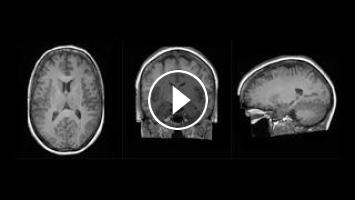

King’s College London, along with partner hospitals and university collaborators, have been developing and deploying AI algorithms to benefit healthcare for decades. The Synthetic Brain Project is focused on building deep learning models that can synthesize artificial 3D MRI images of the human brain. This AI model can help scientists understand what an image of a human brain looks like across a variety of ages, genders, and diseases. Synthetic brain images can help clinical teams understand brain diseases, and the spectrum of healthy brains.

The Synthetic Brain Project runs on Cambridge-1, the UK’s most powerful supercomputer, and enables King’s College London to conduct ground-breaking research and innovation that they previously could have only dreamed of.